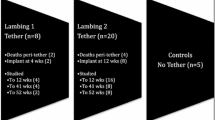

The studies comprised four groups of animals as shown in Table 1. In group 1, eight sheep had a surgically induced right sided scoliosis as previously described [1, 2]: (i) tethering the left lamina of T5–L1 and the left lower six ribs, and (ii) resecting a segment of the right lower six ribs. These animals were implanted with the growth modulating device 3 months after tethering and the results compared with those from 12 sheep (group 2) that were tethered but received no implant (Table 1). In a third group of seven animals the device was implanted at 10 weeks onto a normal spine (group 3) and the growth characteristics compared with those from five controls who had no surgery (group 4). Six was considered a valid number of sheep in the experimental groups to provide sufficient data to produce reproducible results. Two group 1 and one group 2 spare animals allowed for any unforeseen mobidity/mortality.

At 5 weeks, 20 Scottish Blackface lambs underwent surgery to create a right sided scoliosis by (i) tethering the left lamina of T5–L1 and the left lower six ribs and (ii) resecting a segment of their right lower six ribs [1, 2]. Twelve weeks later, through an antero-lateral thoracotomy, a mobile bi-planar hinged implant was inserted onto the right side of the spine of eight animals (group 1). For comparison, 12 sheep were tethered only but had no implant insertion (group 2). In addition, seven had no tethering but were implanted (group 3) and normal growth patterns were observed in five that had no surgery (group 4). Curve progression was assessed by plain radiography and CT over a 1-year period.